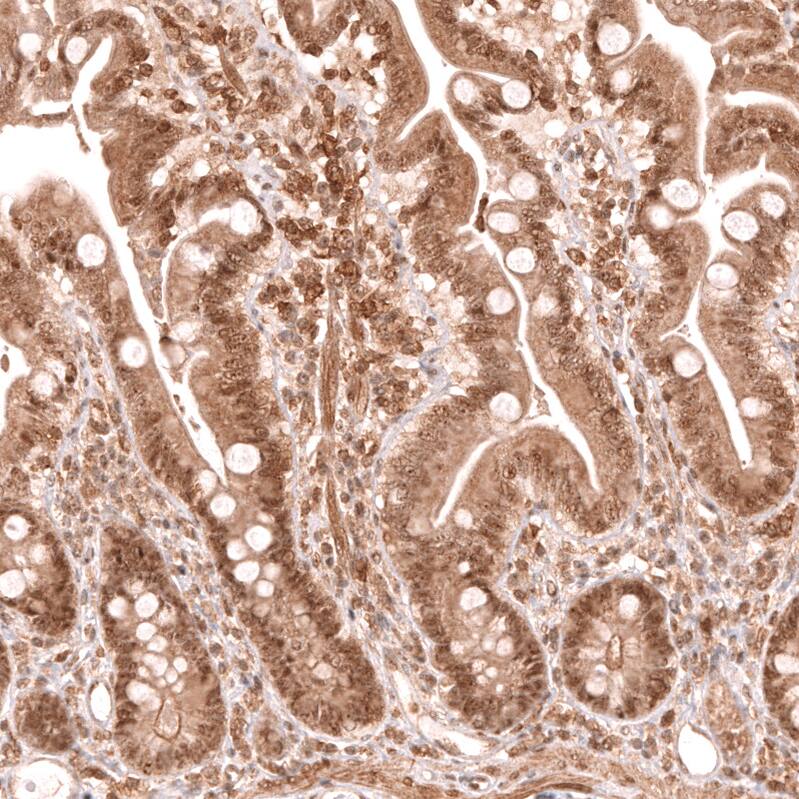

Staining of human small intestine shows strong nuclear positivity in glandular cells.